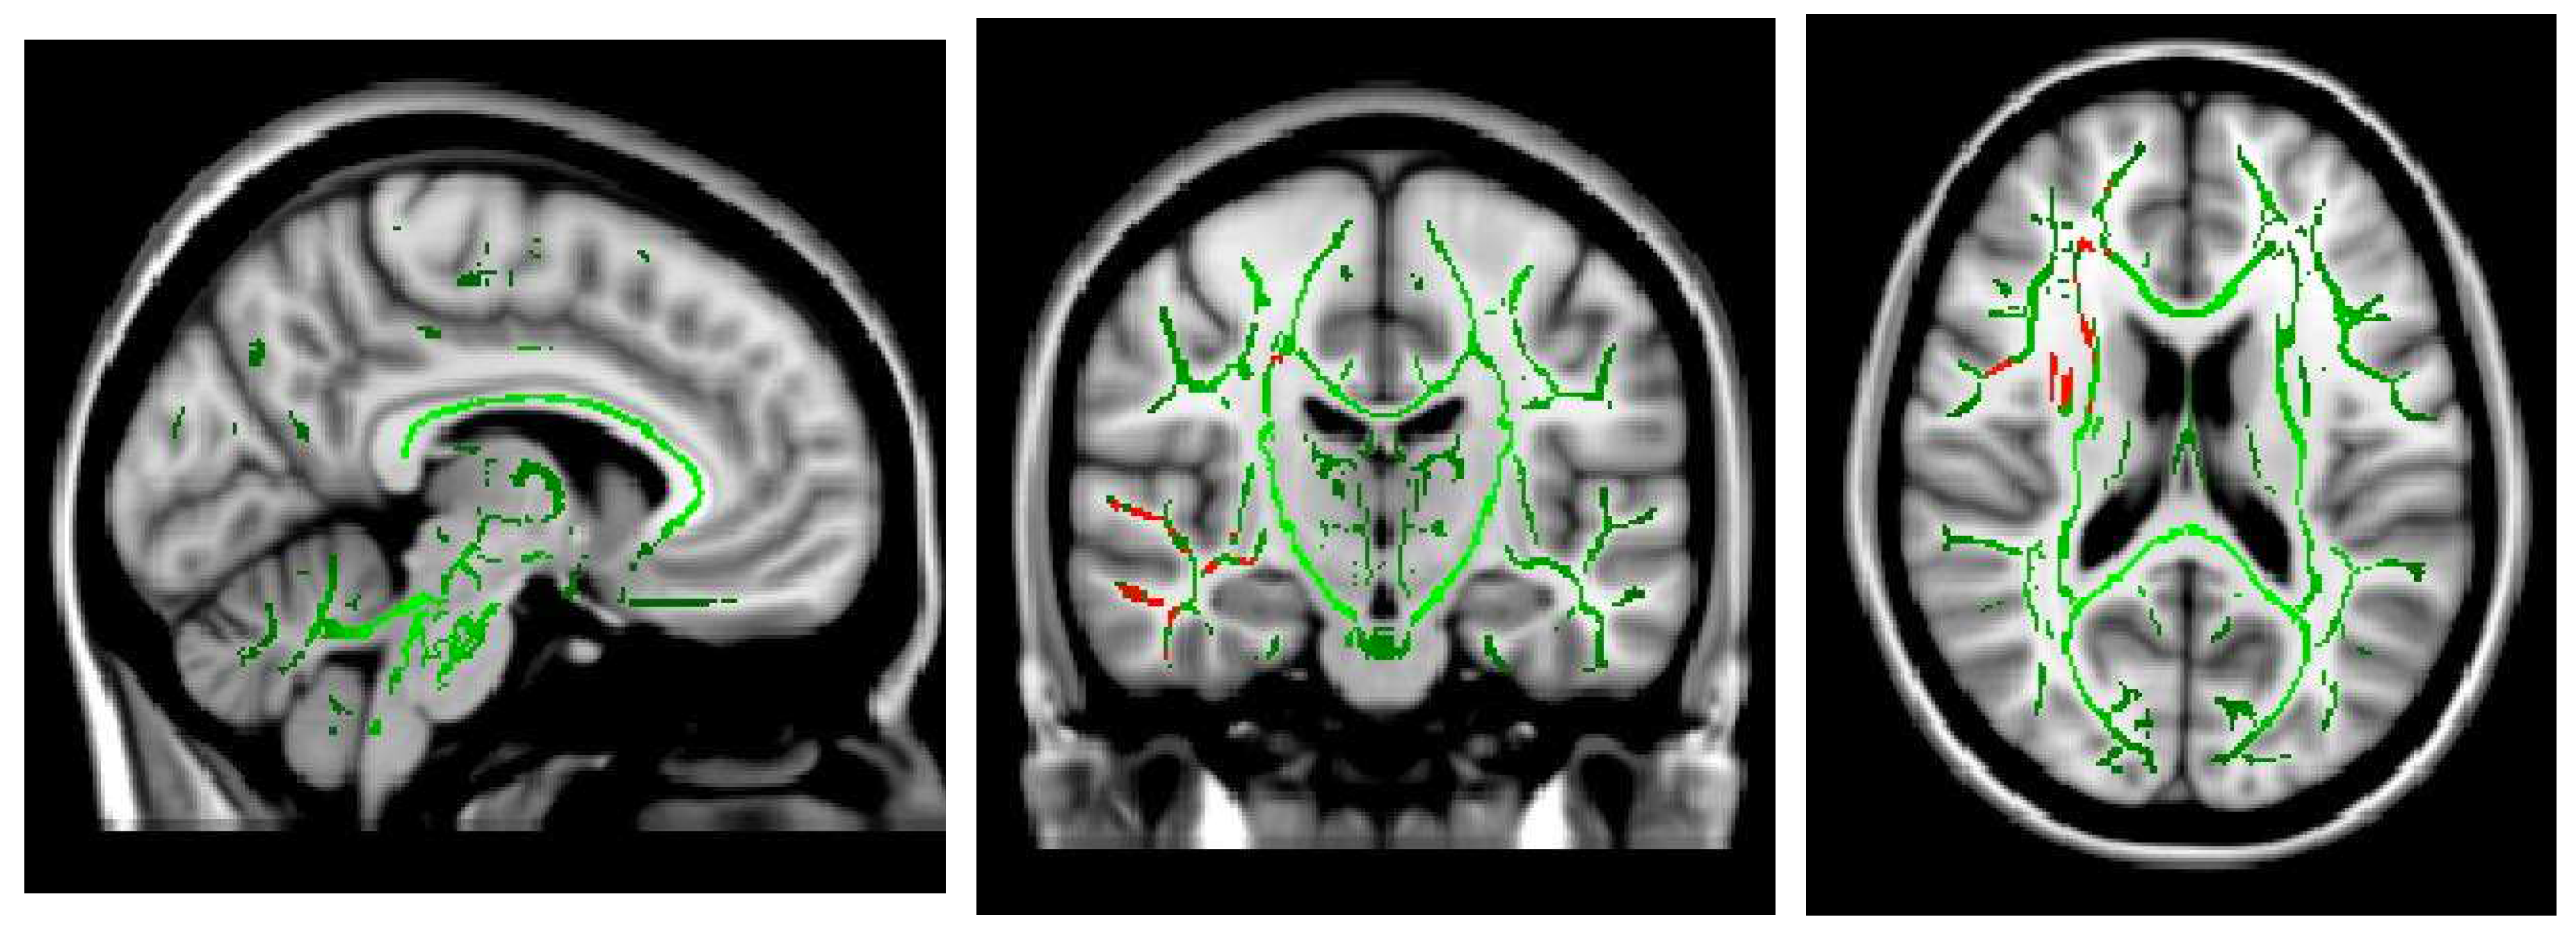

- Shibata Y, Ishiyama S, Matsushita A: White matter diffusion abnormalities in migraine and medication overuse headache: A 1.5-Tesla tract-based spatial statistics study. Clinical Neurology and Neurosurgery 2018, 174, 167–173. [CrossRef]

- Smith SM: Tract-based spatial statistics. NeuroImage 2006, 31, 1487–1505.